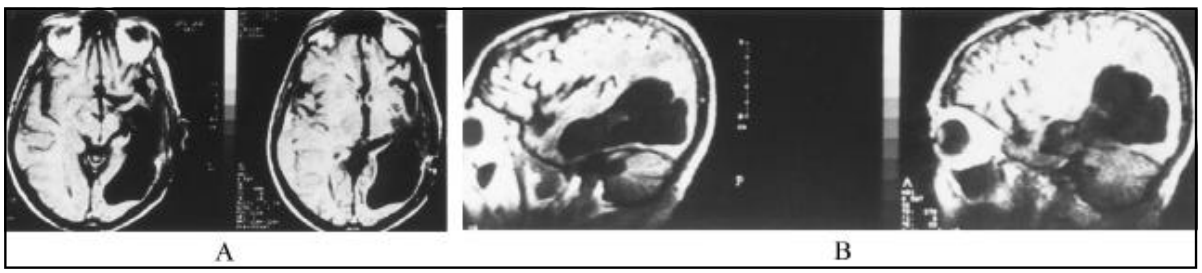

這位67歲的男性患者表現(xiàn)為強(qiáng)烈的頭痛、行為障礙、嘔吐和在過去三個月內(nèi)發(fā)生了兩次局部復(fù)雜癲癇發(fā)作。神經(jīng)學(xué)檢查顯示輕度精神混亂和雙側(cè)乳頭水腫。沒有運(yùn)動或敏感的跡象或癥狀。頭部計(jì)算機(jī)斷層掃描(CT)顯示一個大的左側(cè)顳枕腫塊,彌漫性增強(qiáng)和一些小的低密度區(qū)域位于前部。磁共振成像(MRI)顯示左側(cè)顳葉和枕葉增強(qiáng)病灶,周圍廣泛水腫,并有小腦幕疝(圖1)。

圖1所示。MRI在冠狀面(A)、矢狀面(B)和橫切面(C)顯示左側(cè)顳枕葉增強(qiáng)腫瘤和小腦幕疝。

病灶附近的左幕和硬腦膜強(qiáng)增強(qiáng)。行左側(cè)顳枕葉瓣手術(shù)。正常腦組織與腫瘤之間有一些清晰的區(qū)域。但在其他領(lǐng)域,這些限制就不那么明顯了。腫瘤有強(qiáng)烈的血管蒂。腫瘤浸潤的硬腦膜被切除。腫瘤已被完全切除,從術(shù)后的MRI掃描可以看到(圖2)。

圖2所示。術(shù)后MRI橫切面(A)和矢狀面(B)顯示腫瘤完全切除。